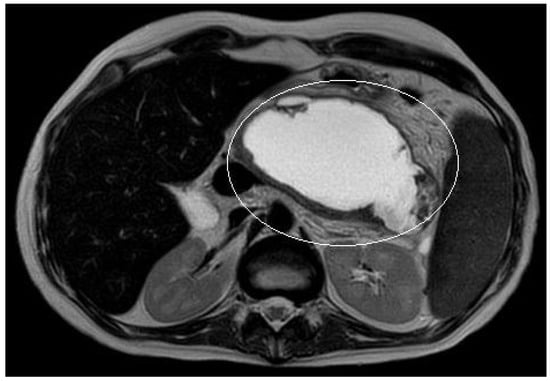

A 15-year boy was affected by B-acute lymphoblastic leukemia and severe coagulopathy; he developed a chemotherapy-induced acute cholecystitis, acute pancreatitis complicated by septic shock and PFC. At MRI the major diameter of the collection was 12 cm (Figure 4). After unsuccessful attempts of conservative treatment, the boy underwent two different attempts of EUS-guided trans-gastric pseudocyst puncture and liquid aspiration, within a month between the two procedures. few days after the second one, the PFCs persisted and the boy still presented abdominal pain and fever. As the need to not delay chemotherapy was pressing, the patient underwent EUS-guided cystogastrostomy and EC-LAMS positioning as a rescue procedure. Post-operative course was uneventful. MRI performed 14 days after the procedure showed a significant reduction of the pseudocyst, which was no longer visible on the ultrasound performed right before its removal. EC-LAMS stayed in place for a total of 28 days and was endoscopically removed, without any intra-operative or post-operative complication.

Figure 4.

Patient n°2 MRI. Pseudocyst with maximum diameter 12 cm in the left hypochondrium in close proximity to the posterolateral wall of the stomach.